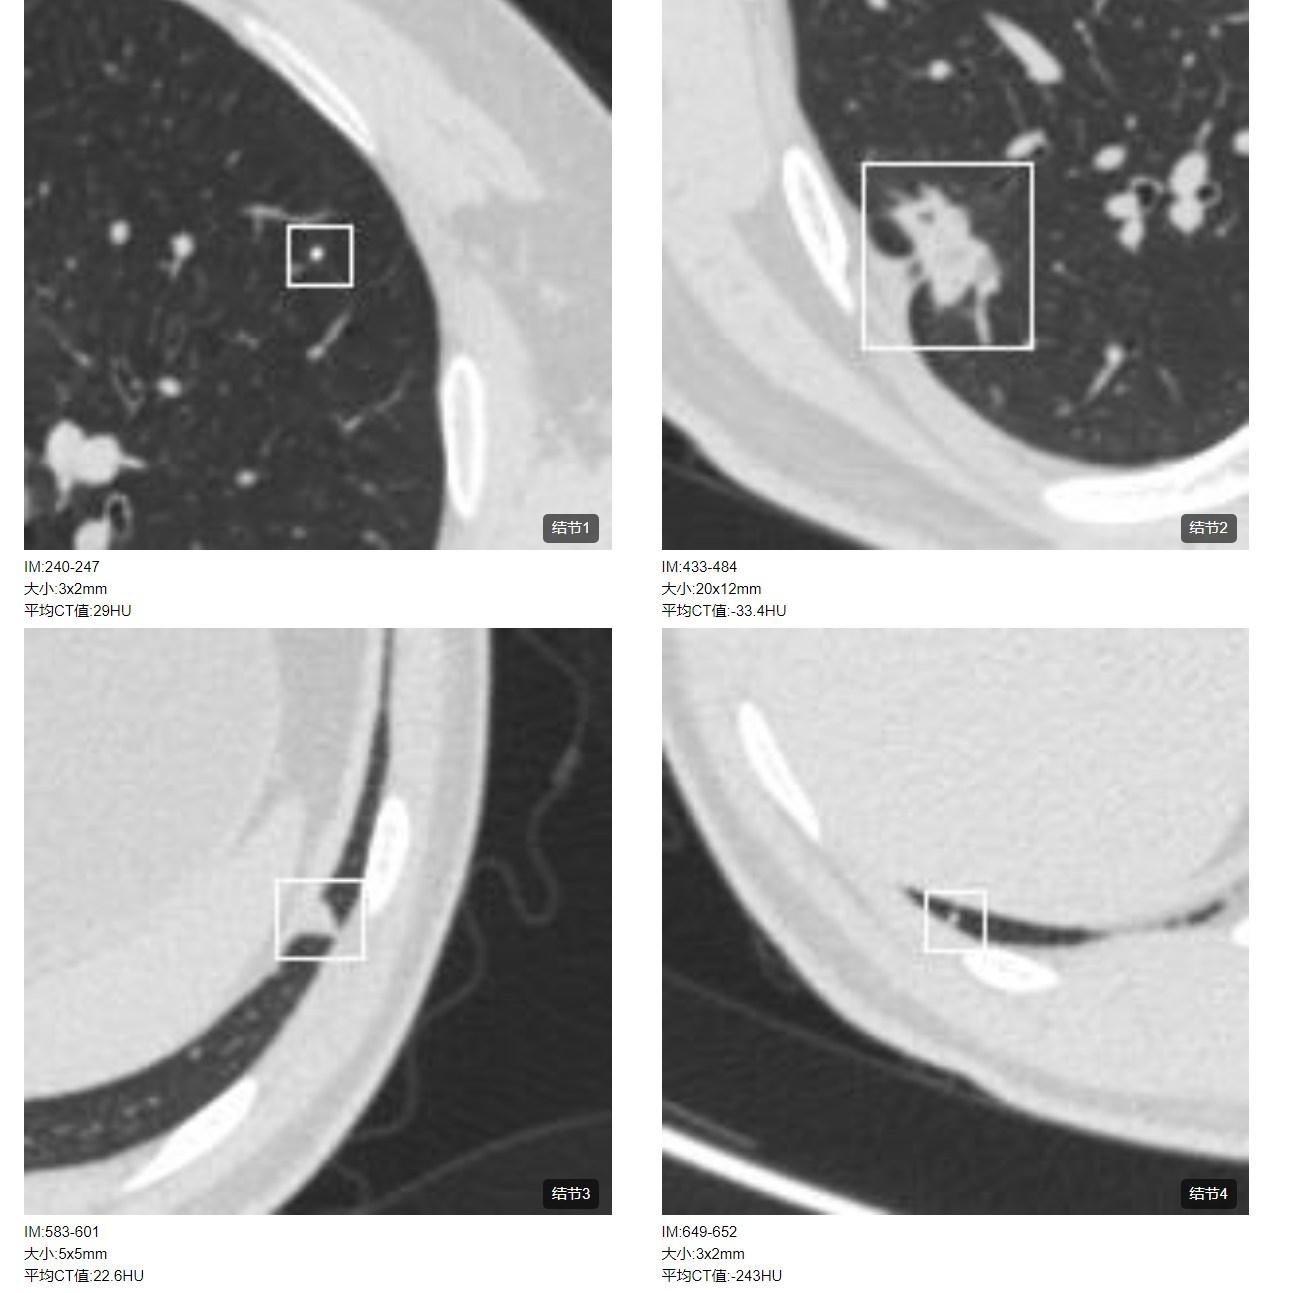

患者1:图2

另外,薄层CT还提示肺内还发现3个结节,从CT上诊断明确,考虑为纤维增殖灶。